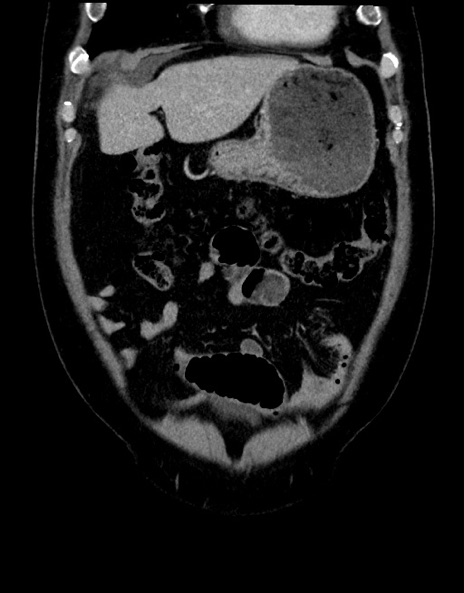

症例15(冠状断像)

【症例】70歳代男性

【主訴】腹痛

【現病歴】今朝から腹痛あり。全体的に痛い。特に左上の方。排ガスが今日はない。冷や汗が出る。

【既往歴】直腸癌術後

【身体所見】左側腹部〜上腹部に圧痛あり。腹膜刺激症状明らかなではない。軽度反跳痛。左下腹部に術後瘢痕あり。

【データ】WBC 7700、CRP 0.02